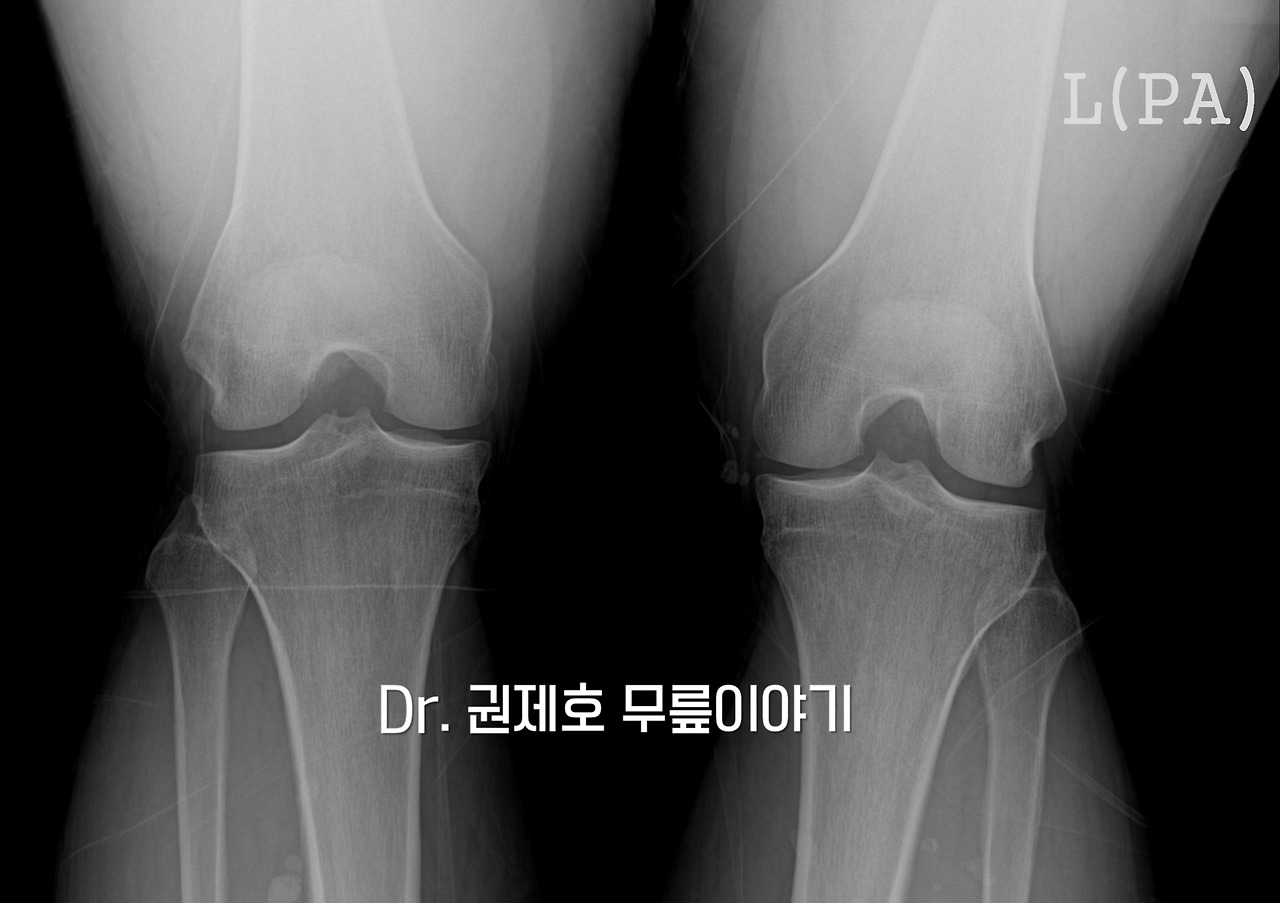

기본 검사는 방사선 사진으로, 무릎 관절에 관여하는 뼈에 이상이 있는지 보는 검사로, 위의 사진을 보면 정상적인 사진입니다. 그 다음은 무릎을 직접 만져보는 이학적 검진을 시행합니다. 검진을 해보니 무릎이 부어있었고, 무릎이 앞으로 빠지는 느낌(Anterior Drawer test)과 비틀었을 때 튕기는 느낌(Pivot shift test)이 있었기에 전방십자인대 손상을 의심해야 했습니다.